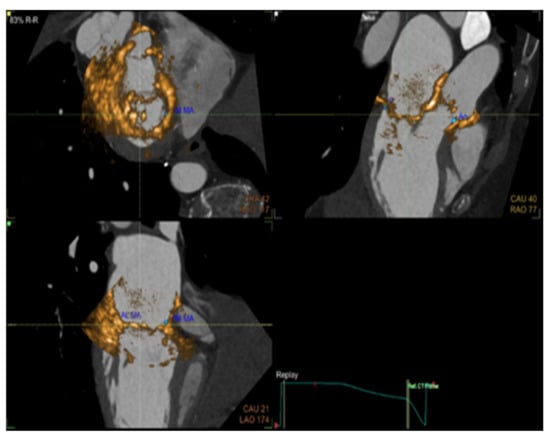

5. Computed Tomography (CT)

Cardiac computed tomography uses multiple X-ray beams emitted by a CT scanner rotating at very high speed and various angles in order to create cross-sectional images. The X-ray beams travel through the body, and they are collected by a detector array that can generate an image. Depending on the path of the beam through tissues of varying densities, a greyscale signal is created. Bone appears white (hyper-dense); the air is black (hypo-dense), blood and muscle are various shades of grey (Figure 11). Contrast is often used in order to enhance differentiation between tissues [21,22]. Coronary angiography also makes use of X-rays in order to visualize the heart vasculature without the need for invasive coronary catheterization. Via software post-analysis we can produce a three-dimensional image of heart vessels and evaluate atherosclerotic and stenotic lesions (Figure 12 and Figure 13). With computed tomography we can also visualize the accumulated calcium that is concentrated in different cardiac structures, such as the mitral annulus and leaflets, aortic cusps, pericardium, and coronary arteries, and quantify it via Agaston units or calcium score. For example, in aortic stenosis with the use of established thresholds of calcium score, we can differentiate between severe forms of the disease in special cases and choose the appropriate treatment for them [23,24]. Additionally, we can calculate the coronary calcium score (CAC), which according to the latest US and European guidelines can be used as a risk modifier in atherosclerotic coronary artery disease with incremental value in primary prevention [25,26,27].

Figure 13. Computed tomography: 3-D reconstruction of the ascending aorta along with the three coronary arteries: left anterior descending (LAD), left marginal branch (LMB).

Applsci 11 10549 g013